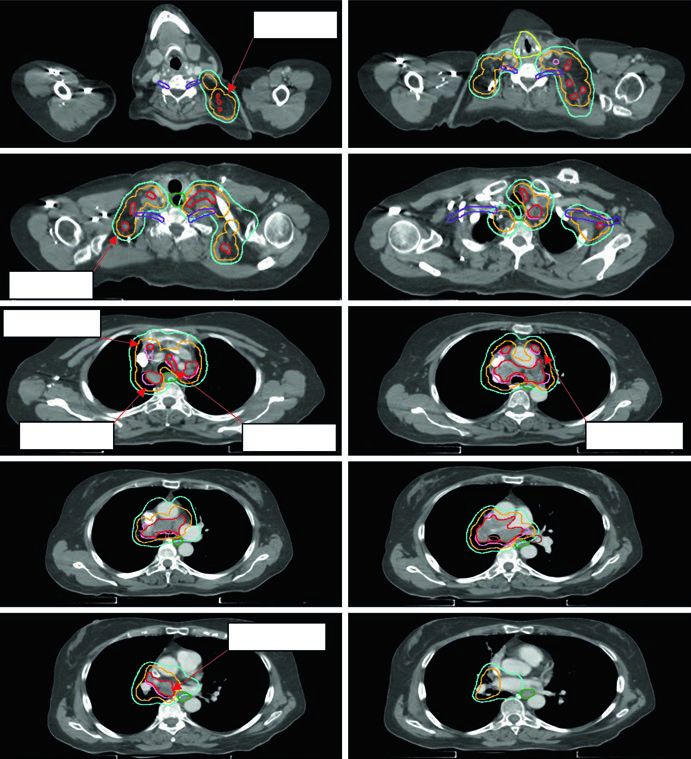

A dose máxima em ponto da PBT é restrita a 55 Gy em qualquer esquema. A Figura 13.2 do texto mostra três casos de estádio inicial: tumor periférico clássico tratado com 54 Gy/3fx, tumor próximo à PBT com 48 Gy/4fx e tumor central com 50 Gy/5fx.

CPNPC localmente avançado (estádios II-III): controle nodal e integração com quimioterapia

No estádio localmente avançado, a expansão iGTV → iCTV aumenta para 0,5 a 0,8 cm, reflexo dos dados histológicos que mostram extensão microscópica significativa no CPNPC. A margem PTV depende do nível de controle de movimento e IGRT implementado:

- 1,0–1,5 cm sem controle de movimento/IGRT

- 0,5–1,0 cm com TC 4D ou CBCT, mas não ambos

- 0,3–0,5 cm com TC 4D + kV/CBCT (abordagem preferida)

A dose padrão para CPNPC estádio II-III com quimioterapia concomitante é 60 Gy em 30 frações (2 Gy/fx). Doses de escalada acima de 60 Gy não demonstraram benefício em ensaios randomizados e aumentaram toxicidade. O GTV inclui tumor primário e linfonodos acometidos visíveis em TC ou PET.

A Figura 13.3 do texto ilustra um caso cT1cN3M0 IIIB: tumor no LSD com linfonodo hilar direito, subcarinal, paratraqueal e SCV direita acometidos. O plano de 60 Gy/30fx cobre todos os sítios PET-positivos com exclusão das cadeias eletivas contralaterais. A Figura 13.4 mostra um caso cT4N3M0 IIIC com SCV bilateral comprometida e síndrome de veia cava superior, exigindo campo que inclui mediastino superior bilateral.